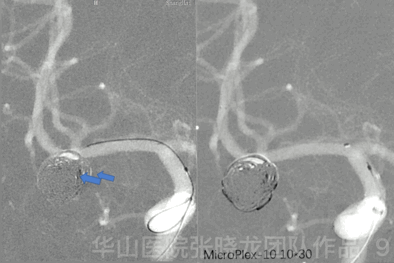

Figure 8. Then the aneurysm sac was packed with MicroPlex-10 coils to ensure full deployment of the stent. Five MicroPlex-10 10mm*30cm coils were packed within the frame, and the superior branch was spanserved well.

Figure 9 GIF. To fill the outflow tract.

Figure 10 GIF. Angiography shows the remnant of the inflow tract.

Figure 11 GIF. MicroPlex-10 5mm*15cm (x4) coils were inserted for packing the inflow tract of the aneurysm.

Figure 12 GIF. Post-operative angiography shows the densely packing of the aneurysm with the parent artery patent. Tirofiban (Xinweining) 12ml was administrated.